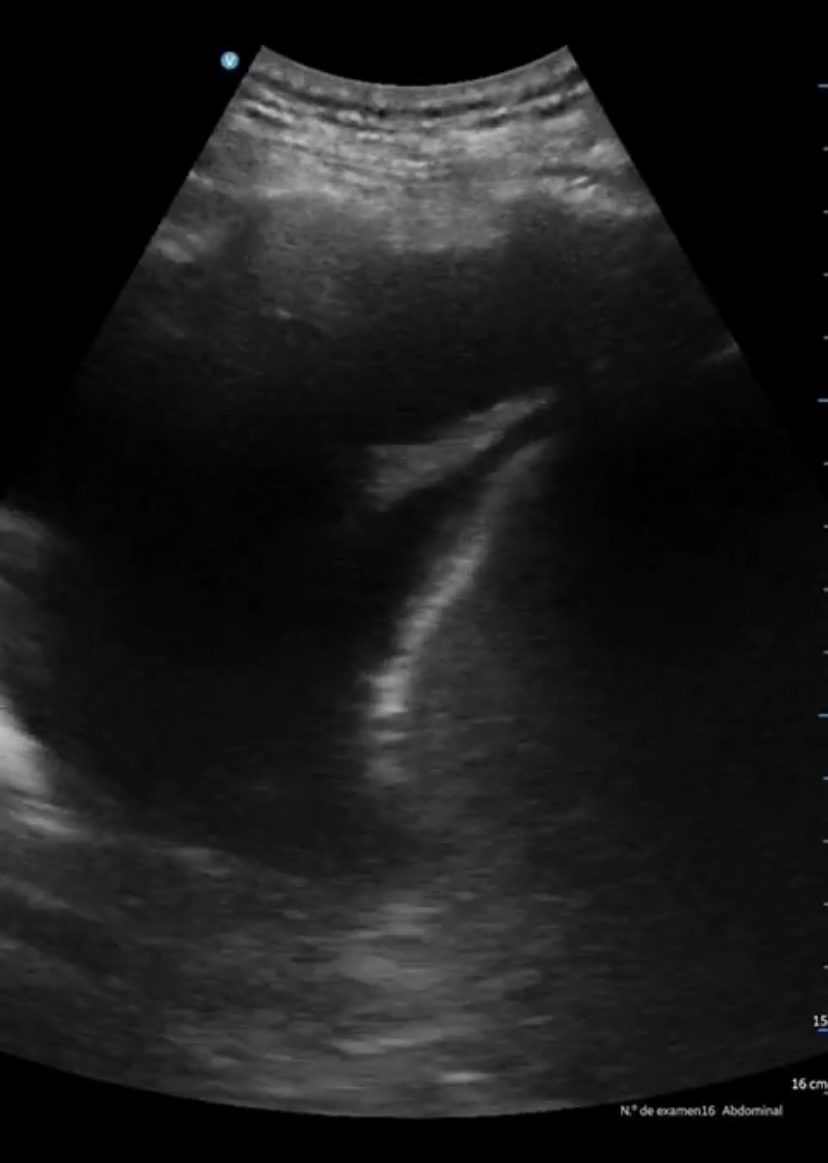

Se aprecia atelectasia lobar media con derrame pleural derecho de unos 150 cc, signo de la medusa. Líneas B en patrón B3 en ambas bases. Cavidades cardiacas normales con correcto funcionamiento valvular, adecuada contractilidad sin indicios de derrame pericárdico. Aumento de vena cava de 2,57 cm no colapsable.